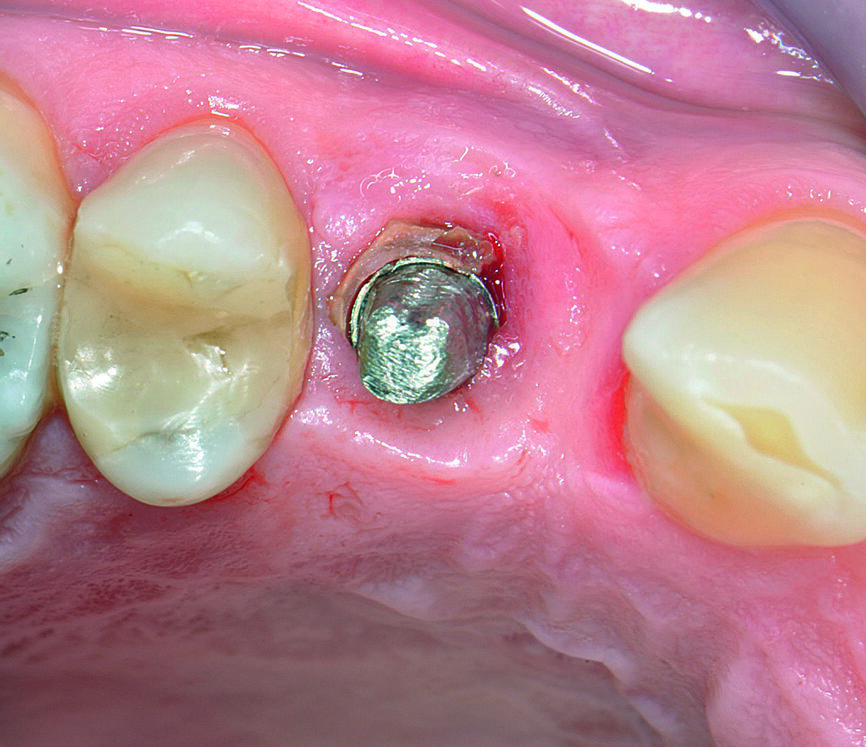

Dans le domaine dentaire, la parodontite est l’une des principales maladies chroniques non transmissibles. Les spécialistes de la parodontologie et les scientifiques internationaux ont élaboré divers principes de prévention des maladies parodontales.2 La péri-implantite est une version du XXIe siècle de la parodontite et sa fréquence s’accroît avec l’augmentation du nombre d’implants posés (Figs. 1–3). Tout comme la parodontite, cet état pathologique est associé au biofilm, mais au lieu de toucher les desmodontes et les tissus osseux, elle se caractérise par une inflammation de la muqueuse péri-implantaire et la perte progressive de l’os de soutien.3 Les préoccupations majeures dans ce problème sont liées au rôle déterminant que peuvent jouer de multiples facteurs de risque incriminés dans l’étiologie4 et l’absence d’un traitement de référence. Les mesures de prévention primaires et secondaires sont réellement importantes pour éviter la survenue d’une mucite et d’une péri-implantite ainsi que les récidives, mais de nombreux détails doivent être pris en considération avant une pose d’implants de façon à minimiser les problèmes iatrogènes. Outre les implants, les solutions prothétiques que peuvent proposer les professionnels de la santé buccodentaire aux patients sont nombreuses et diverses s’il est tenu compte de la situation globale du début jusqu’à la fin. Les implants peuvent ne pas toujours être dans le meilleur intérêt d’un patient. Par conséquent, avant la pose d’un implant, chaque clinicien devrait évaluer non seulement les aspects spécifiques du patient et du site implantaire, mais également les compétences du chirurgien, du chirurgien-dentiste, de l’hygiéniste buccodentaire et du prothésiste dentaire afin de minimiser le risque de péri-implantite dans le futur. Il est nécessaire de procéder à l’examen des points suivants avant la prévention primaire et secondaire, une approche que nous appelons dans notre article, la « Prévention 0 ».

Aspects particuliers liés au site implantaire

Le processus de cicatrisation après une perte dentaire entraîne une réduction variable du processus alvéolaire et, de ce fait, des lésions des tissus durs et mous. Le clinicien doit évaluer soigneusement tous les sites exposés aux situations suivantes car elles présentent un risque de troubles majeurs de cicatrisation : perte du soutien parodontal, infections endodontiques, fractures radiculaires longitudinales, faible épaisseur des plaques osseuses vestibulaires, positionnement vestibulaire/lingual des dents par rapport à l’arcade, extraction avec traumatisme accru des tissus, lésions, pneumatisation du sinus maxillaire, médicaments et maladies systémiques réduisant la quantité de tissu osseux formé naturellement, agénésie dentaire et points de pression dus aux prothèses amovibles à appui muqueux. D’autres aspects liés au site concernent la connaissance anatomique et particulièrement la structure anatomique adéquate du site considéré (sinus maxillaire, nerf alvéolaire inférieur), la santé endodontique et parodontale des dents adjacentes, et le phénotype du patient. Selon Linkevicius et al., il existe des éléments probants montrant qu’un tissu mou de faible épaisseur entraîne une perte accrue d’os marginal par rapport à un tissu mou épais autour d’un implant.3, 8 Le manque de tissu osseux a conduit au développement d’autres techniques chirurgicales permettant d’éviter des procédures majeures de régénération osseuse ou de greffe, notamment l’utilisation d’implants courts, d’implants inclinés, d’implants ptérygoïdiens et d’implants palatins, dont les résultats étaient discutables mais réduisaient manifestement les possibilités de nettoyage et d’entretien des implants et des prothèses.